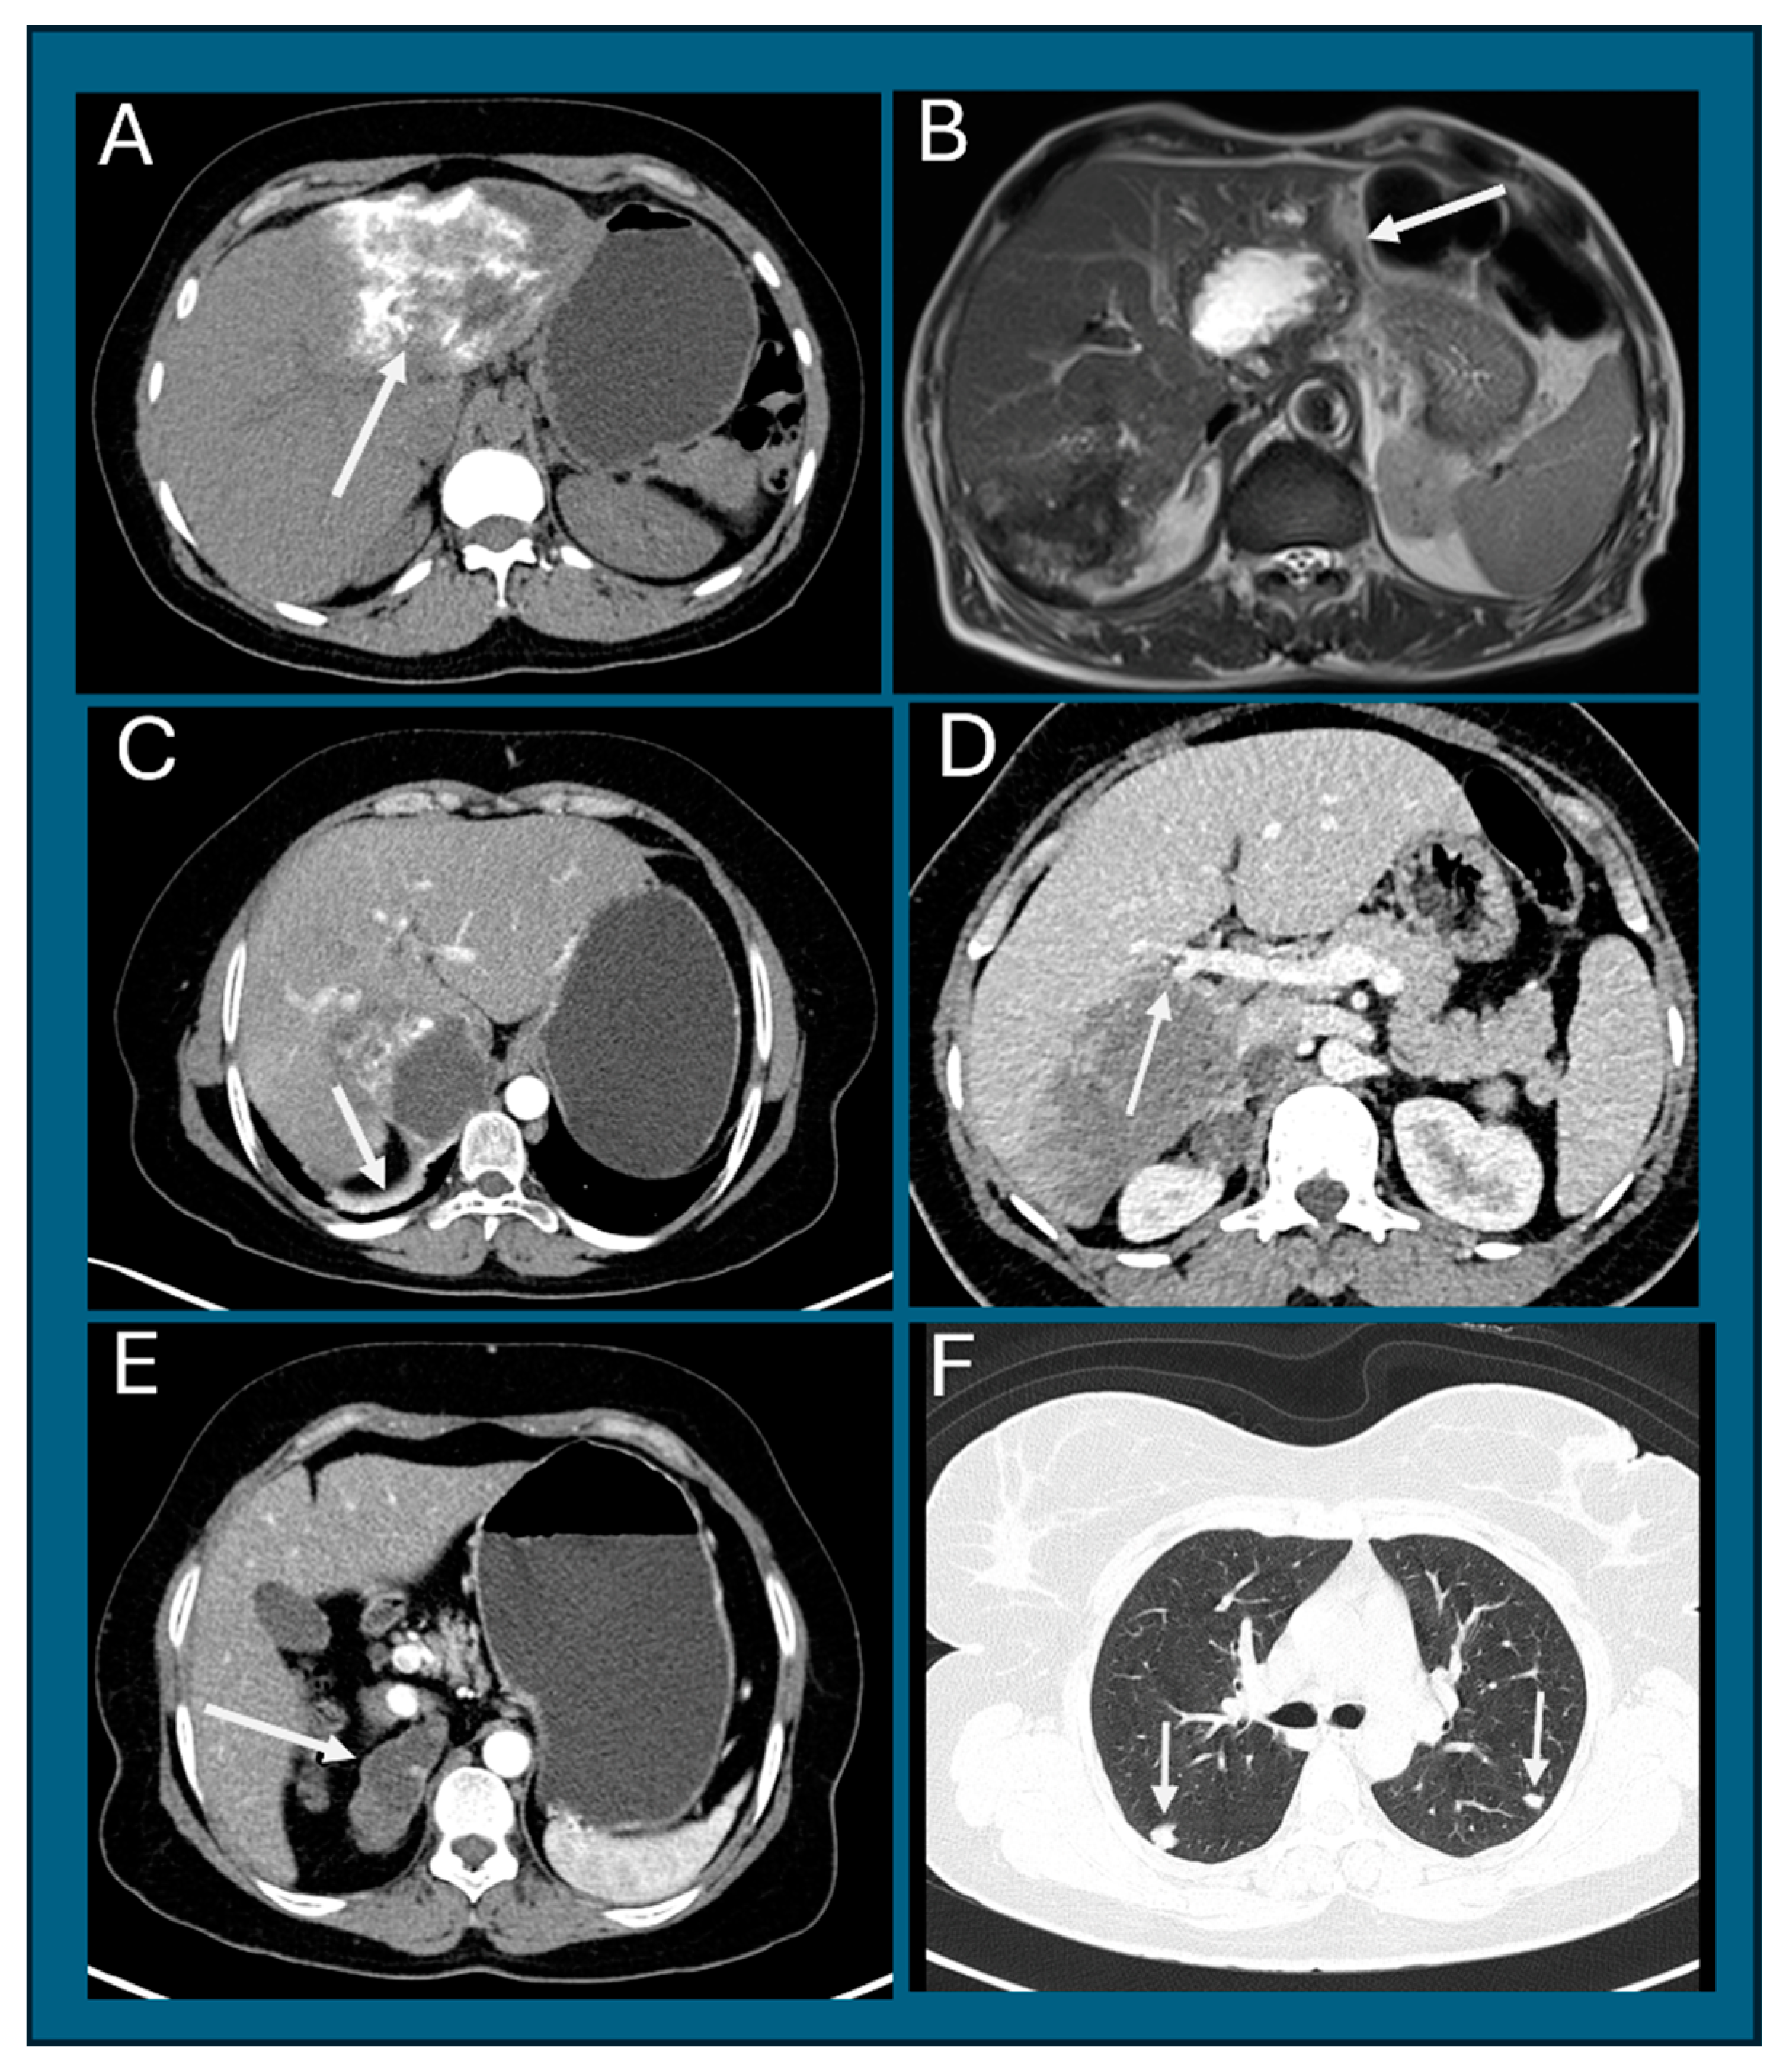

- Parry, A.H.; Wani, A.H.; Feroz, I. The spectrum of multimodality imaging findings in hepatic alveolar echinococcosis and the potential role of diffusion-weighted imaging in its characterisation. Pol. J. Radiol. 2020, 85, e613–e623. [Google Scholar] [CrossRef] [PubMed]

- Calame, P.; Weck, M.; Busse-Cote, A.; Brumpt, E.; Richou, C.; Turco, C.; Doussot, A.; Bresson-Hadni, S.; Delabrousse, E. Role of the radiologist in the diagnosis and management of the two forms of hepatic echinococcosis. Insights Imaging 2022, 13, 68. [Google Scholar] [CrossRef]

- Bulakçı, M.; Kartal, M.G.; Yılmaz, S.; Yılmaz, E.; Yılmaz, R.; Şahin, D.; Aşık, M.; Erol, O.B. Multimodality imaging in diagnosis and management of alveolar echinococcosis: An update. Diagn. Interv. Radiol. 2016, 22, 247–256. [Google Scholar] [CrossRef]

- Kodama, Y.; Fujita, N.; Shimizu, T.; Endo, H.; Nambu, T.; Sato, N.; Todo, S.; Miyasaka, K. Alveolar echinococcosis: MR findings in the liver. Radiology 2003, 228, 172–177. [Google Scholar] [CrossRef] [PubMed]

- Brumpt, É.; Liu, W.; Graeter, T.; Calame, P.; Rong, S.; Jiang, Y.; Li, W.; Bao, H.; Delabrousse, É. Kodama-XUUB: An informative classification for alveolar echinococcosis hepatic lesions on magnetic resonance imaging. Parasite 2021, 28, 66. [Google Scholar] [CrossRef] [PubMed]